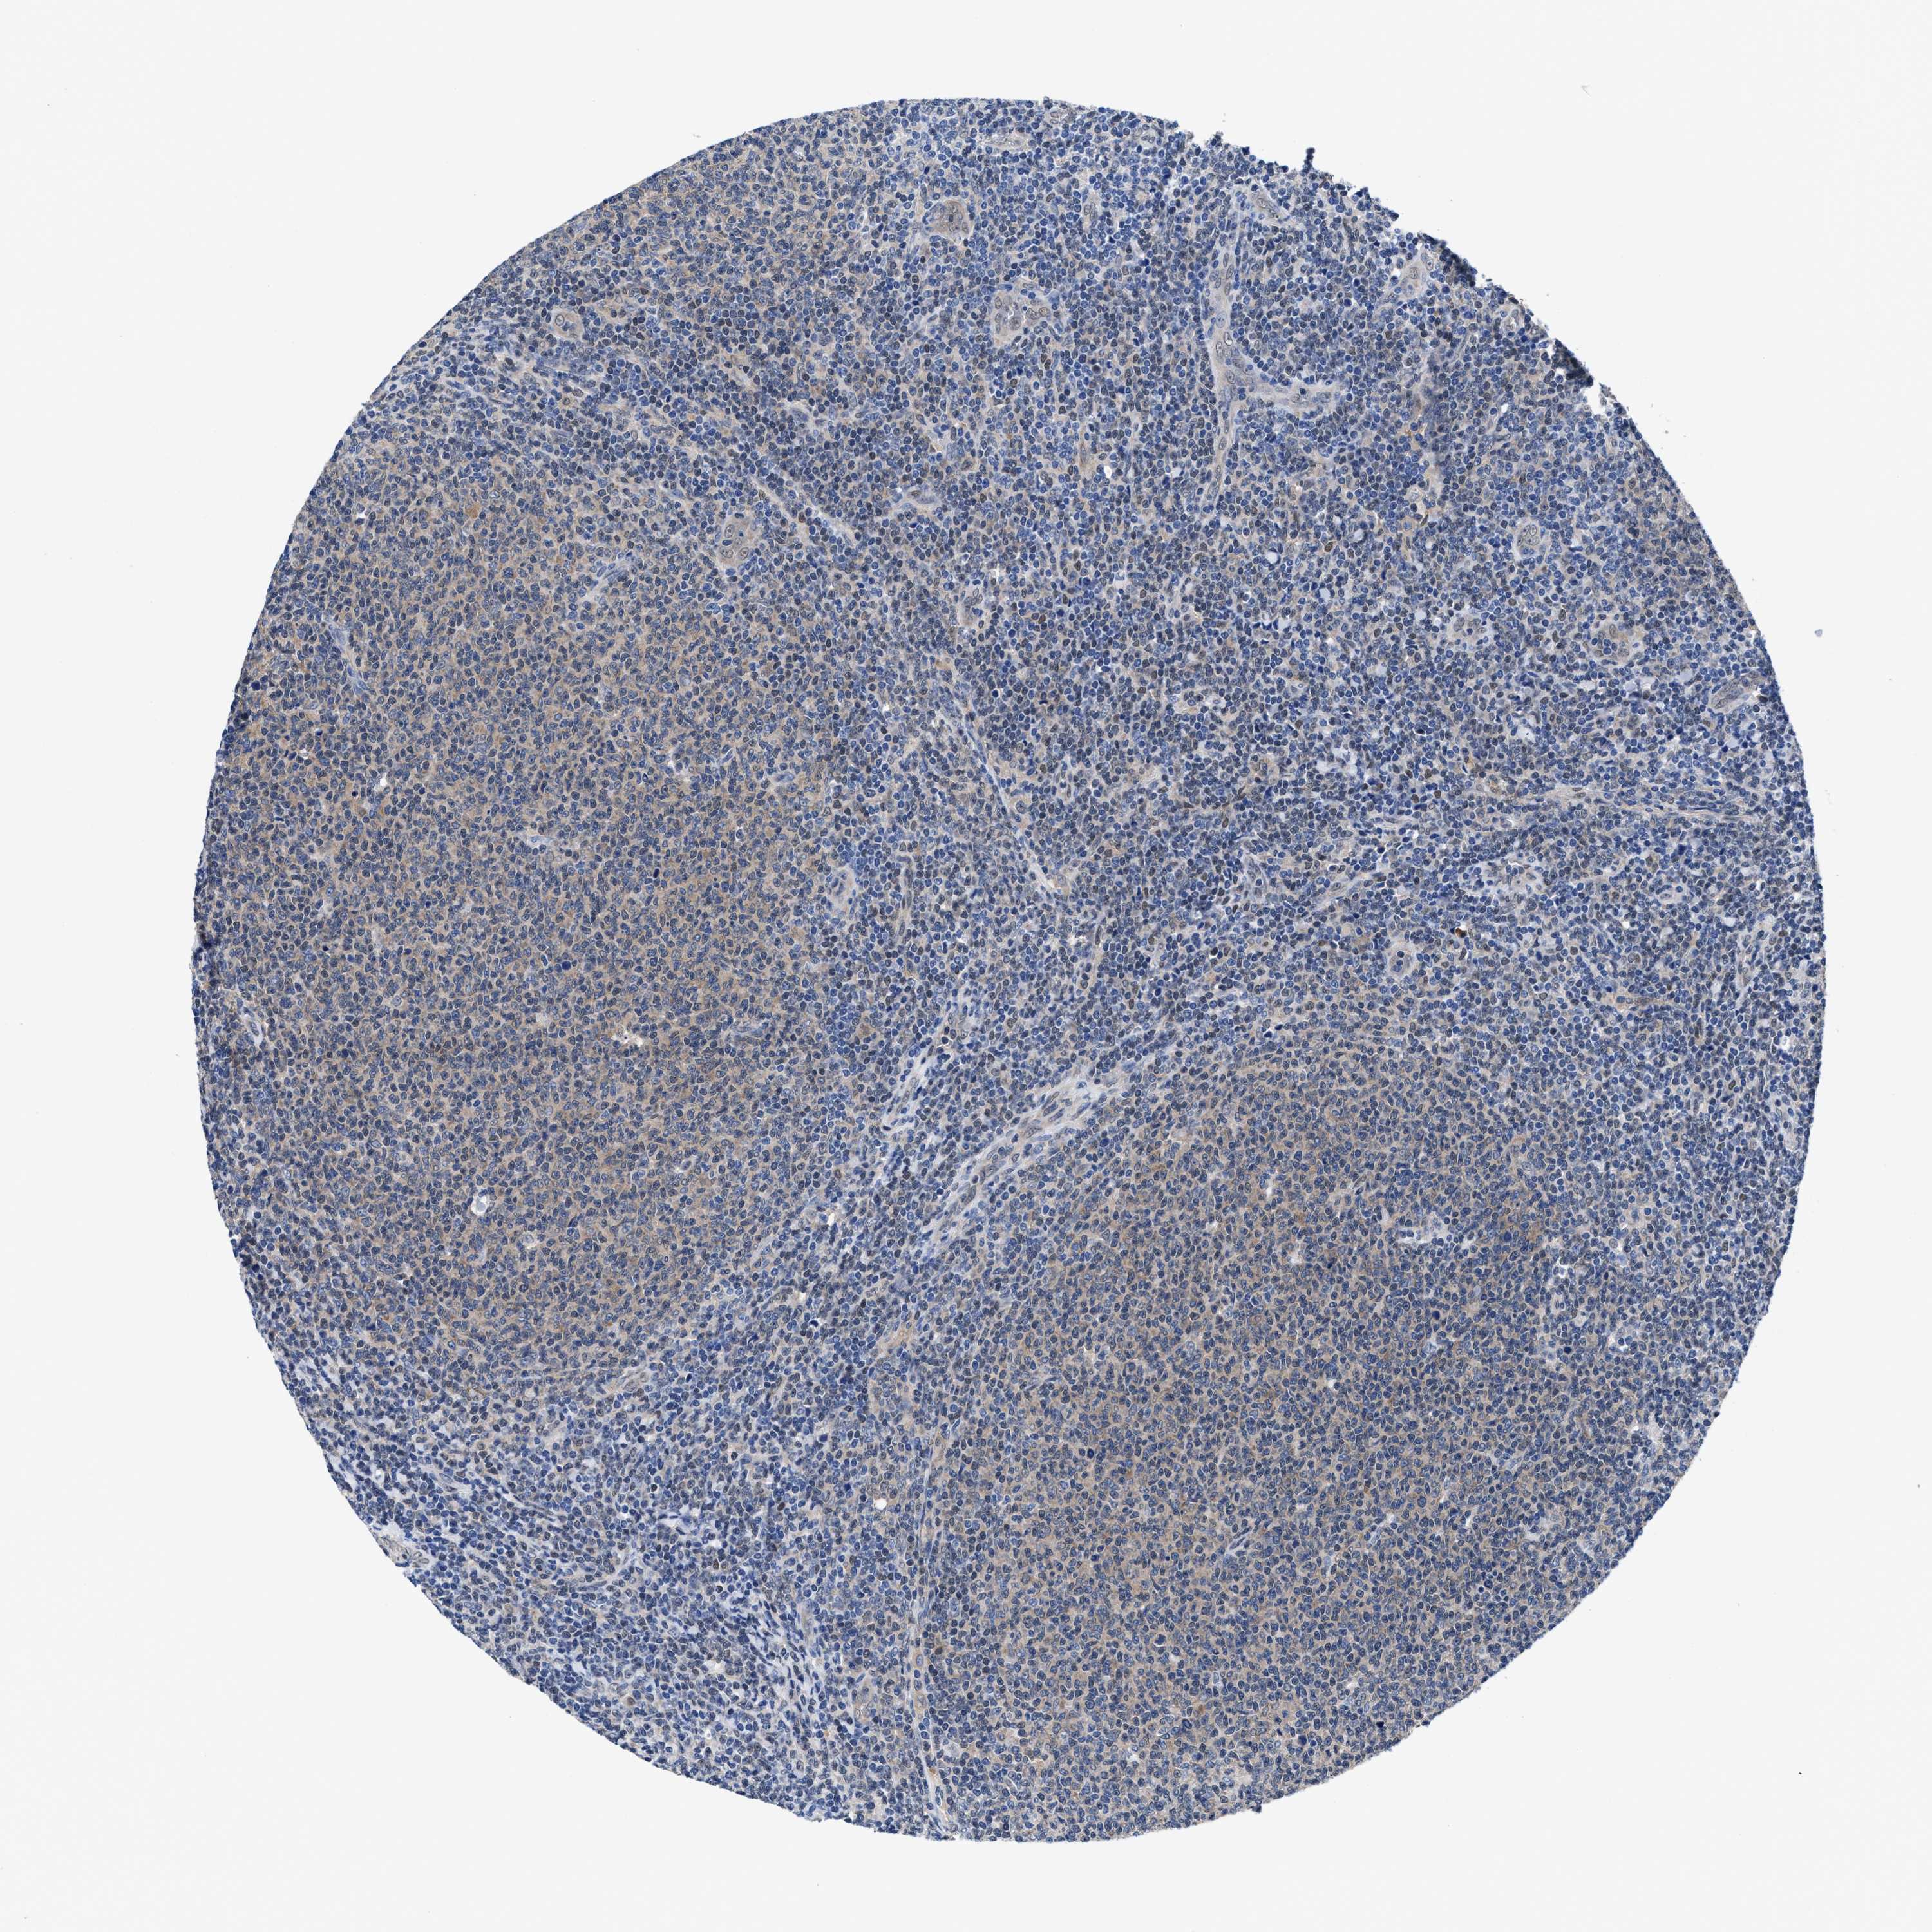

CANCER LYMPHOMA Show tissue menu

LYMPHOMA - Protein expressioni

A mouse-over function shows sample information and annotation data. Click on an image to view it in a full screen mode. Samples can be filtered based on level of antibody staining by selecting one or several of the following categories: high, medium, low and not detected. The assay and annotation is described here.

Antibody stainingi

Antibody staining in the annotated cell types in the current human tissue is reported as not detected, low, medium, or high, based on conventional immunohistochemistry profiling in selected tissues. This score is based on the combination of the staining intensity and fraction of stained cells.

Each image is clickable and will lead to virtual microscopy that enables deeper exploration of all samples and also displays staining intensity scores, fraction scores and subcellular localization as well as patient and tissue information for each sample.

HPA022434

Staining

Medium

Low

Intensity

Moderate

Quantity

75%-25%

Location

Nuclear

Hodgkin's disease, NOS

Malignant lymphoma, non-Hodgkin's type, High grade

Malignant lymphoma, non-Hodgkin's type, Low grade